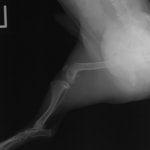

症例3:キルシュナーワイヤーのピンニングによる整復

ペルシャ猫 11ヶ月齢 雄

他院にて左大腿骨遠位の成長板骨折(salter-harrisⅠ型)が認められており、治療相談を目的として来院。当院にて、キルシュナーワイヤーを用いたピンニングにより骨折部位の整復を行いました。術後の経過は良好で、現在も経過観察中です。

術後レントゲン